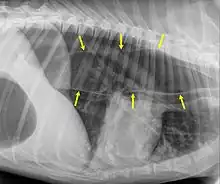

Megaesophagus, also known as esophageal dilatation, is a disorder of the esophagus in humans and other mammals, whereby the esophagus becomes abnormally enlarged. Megaesophagus may be caused by any disease which causes the muscles of the esophagus to fail to properly propel food and liquid from the mouth into the stomach (that is, a failure of peristalsis). Food can become lodged in the flaccid esophagus, where it may decay, be regurgitated, or maybe inhaled into the lungs (leading to aspiration pneumonia).[1]